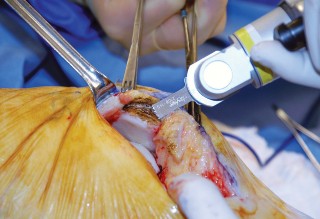

الشق الجراحي:

يُستخدم شق طولي في الجانب الإنسي (الداخلي) من الركبة. يجب أن يكون الشق كبيرًا بما يكفي لتوفير رؤية جيدة للمفصل الرضفي الفخذي وإمكانية التحويل إلى TKA.

- فتح المفصل (Arthrotomy): يكون الفتح خطيًا وموازياً لألياف الوتر الرضفي، ويمتد إلى عظم الظنبوب وإلى الجزء السفلي من الرضفة.

- تحرير الأنسجة الرخوة: يتم قطع الغضروف الهلالي لتحرير الأنسجة الرخوة من عظم الظنبوب، ويتم تطوير سديلة تحت السمحاق في نمط دائري حول الظنبوب. يُمدد هذا التحرير خلفيًا لضمان توازن الأربطة.

-

تصحيح التشوه:

الهدف هو تحقيق تصحيح طفيف للتشوه، مع وجود رخاوة كاذبة طفيفة عند تطبيق ضغط تفحجي في نهاية الإجراء. يجب تجنب التصحيح المفرط.